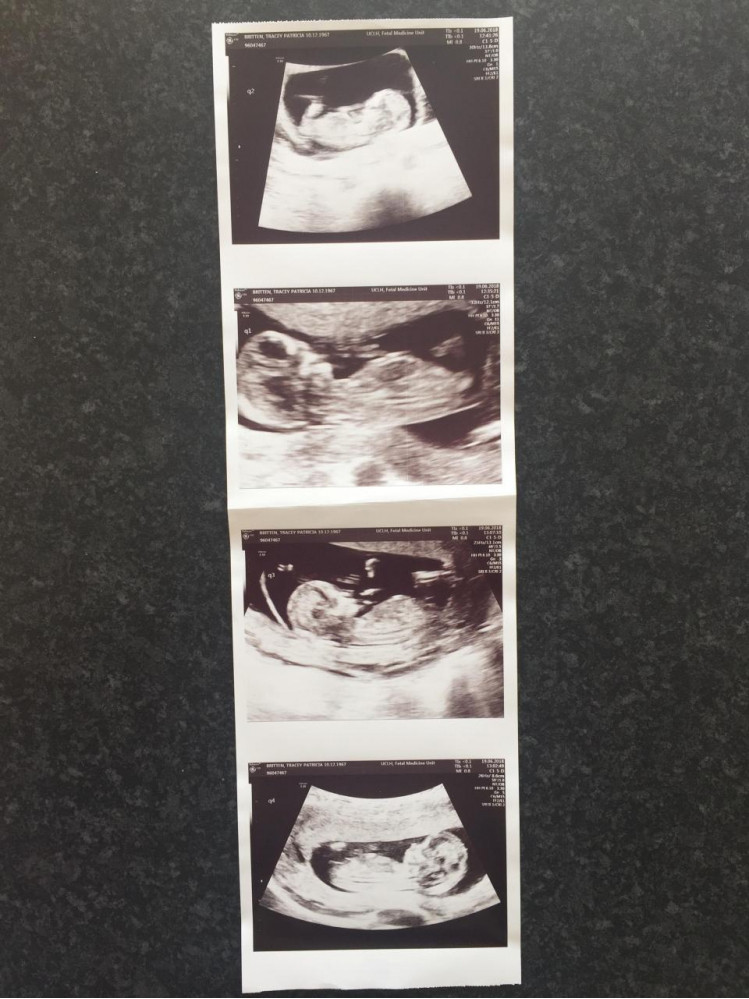

50-летняя жительница Британии беременна четырьмя детьми

50-летняя мать троих дочерей и бабушка восьми внуков беременна еще четырьмя детьми — тремя девочками, две из которых родятся близняшками, и мальчиком. Как сообщает The Sun, ради этого Трейси Бриттен потратила 7 тысяч фунтов (более 60 тысяч рублей) на искусственное оплодотворение.

Сейчас без пяти минут мать семерых детей находится на 25-й неделе беременности. Врачи планируют провести Кесарево сечение через семь недель и надеются, что у этой истории будет счастливый конец.